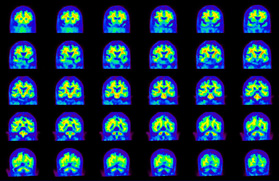

Head / Case4 : Amyloid

Coronal

Courtesy : Kindai University Hospital

- Imaging protocol

- Injected dose: 3.21 MBq/kg, 18F-Flutemetamol

- Uptake time: 100 minutes

- Scan time: 20 minutes